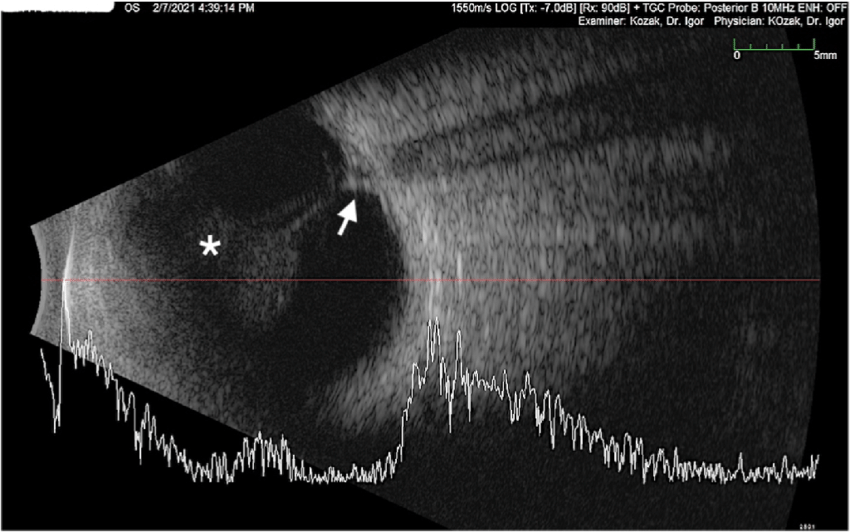

Vitreous hemorrhage

In B-scan, vitreous hemorrhage appears as low-to-medium reflective, mobile dot-like or clump-like echoes within the vitreous cavity. These echoes move with eye movements and may obscure the view of the retina, especially in dense hemorrhage.